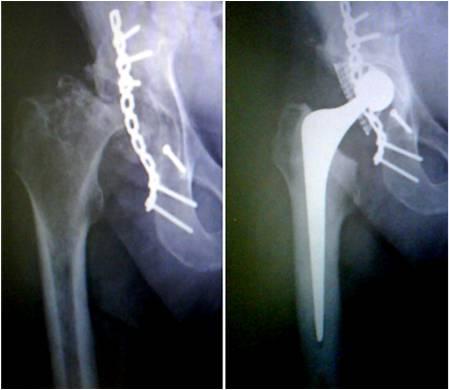

Revision Hip with larger stem for a case where there is loss of bone surrounding the original stem of the 1st hip replacement.

A case where there is a fracture of femur bone after 14 years of primary surgery. This challenge was solved by removal of the original hip and reinserting a long stem Uncemented hip.